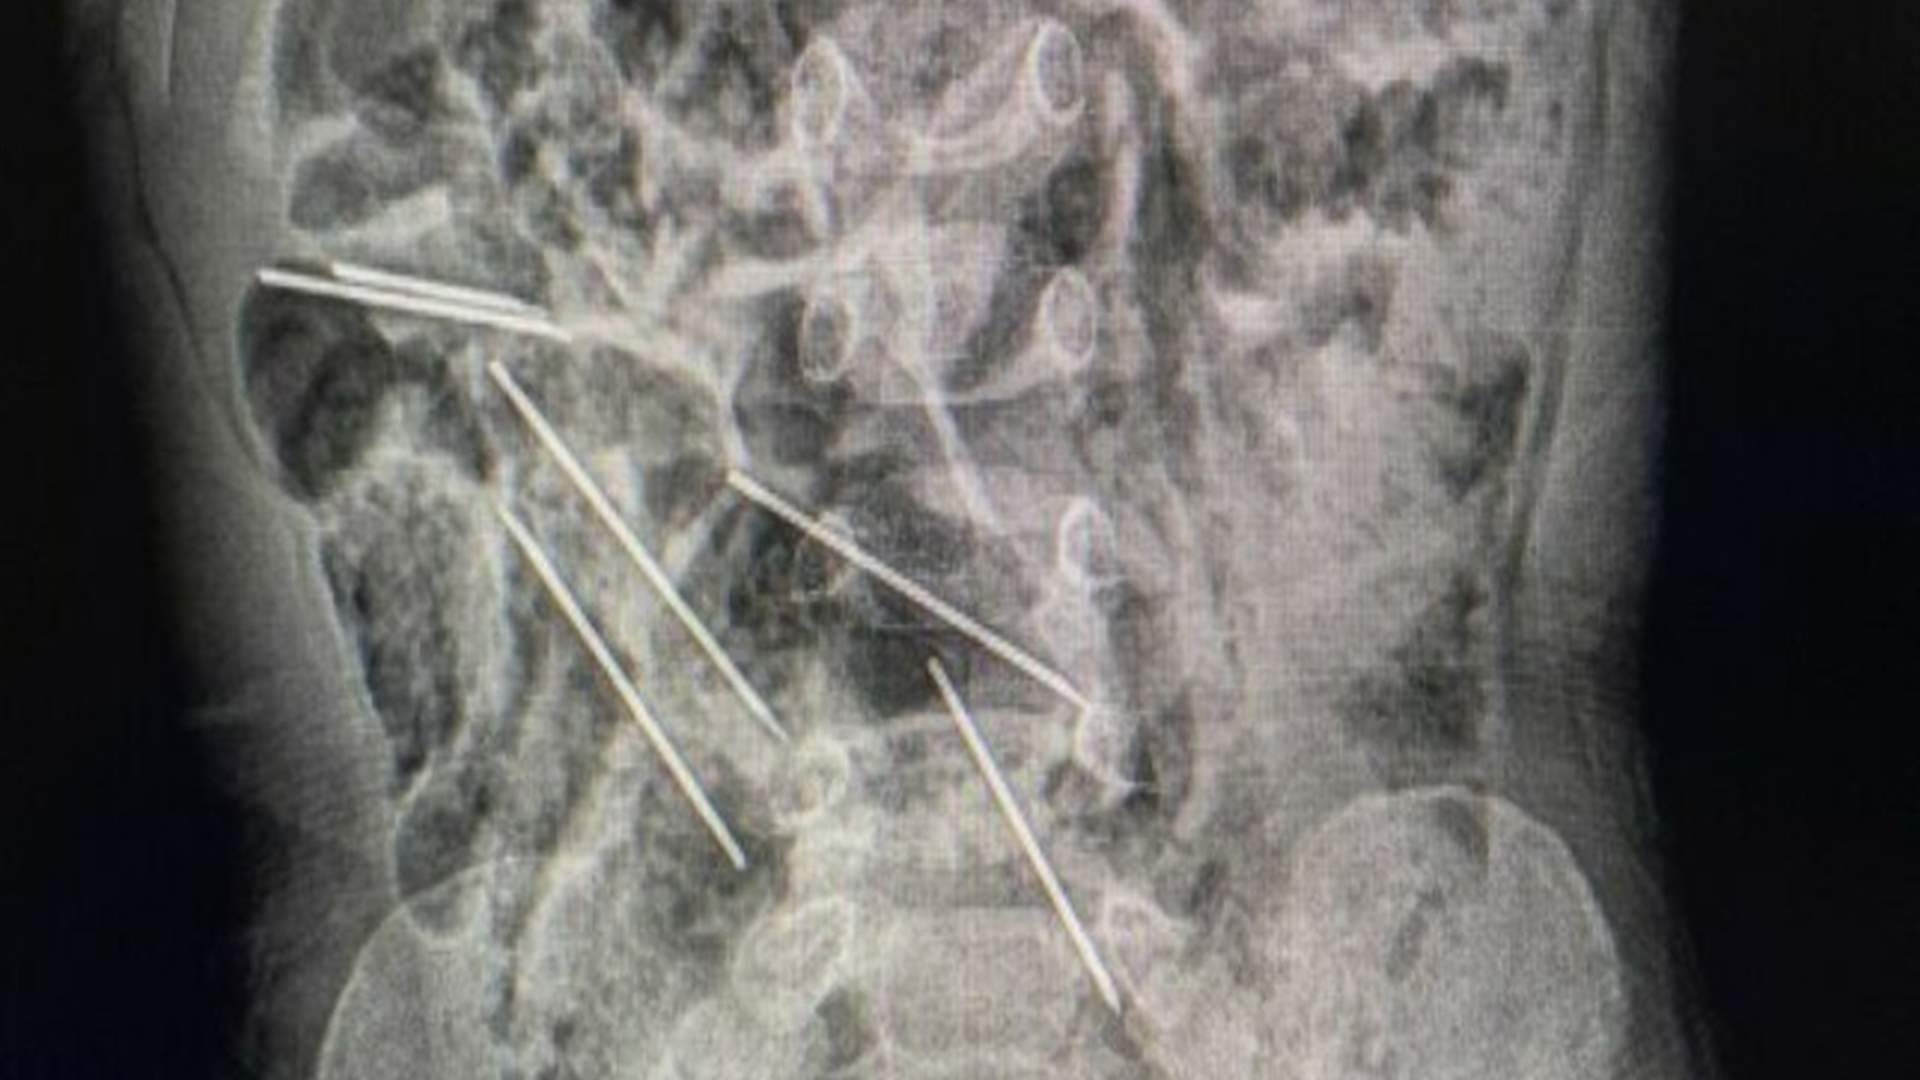

طفل ابتلع ثماني إبر طبية...إليكم ما حصل!

أنقذ الأطباء في شمال شرق بيرو طفل يبلغ من العمر عامين، بعد أن ابتلع ثماني إبر أثناء اللعب.

وقال الدكتور إفراين سالازار: "عندما كنا في غرفة العمليات وفتحنا بطنه، وجدنا تلك القطع المعدنية، وأدركنا أنها كانت في الحقيقة إبرًا".

ويُذكر أن هذه الإبر هي لتطعيم حيوانات المزرعة حيث تعمل والدة الصبي.

وقالت الوالدة إنه ربما ابتلعها عندما كان يلعب هناك، علماً أن حالته الصحية أصبحت مستقرة بعد الجراحة.